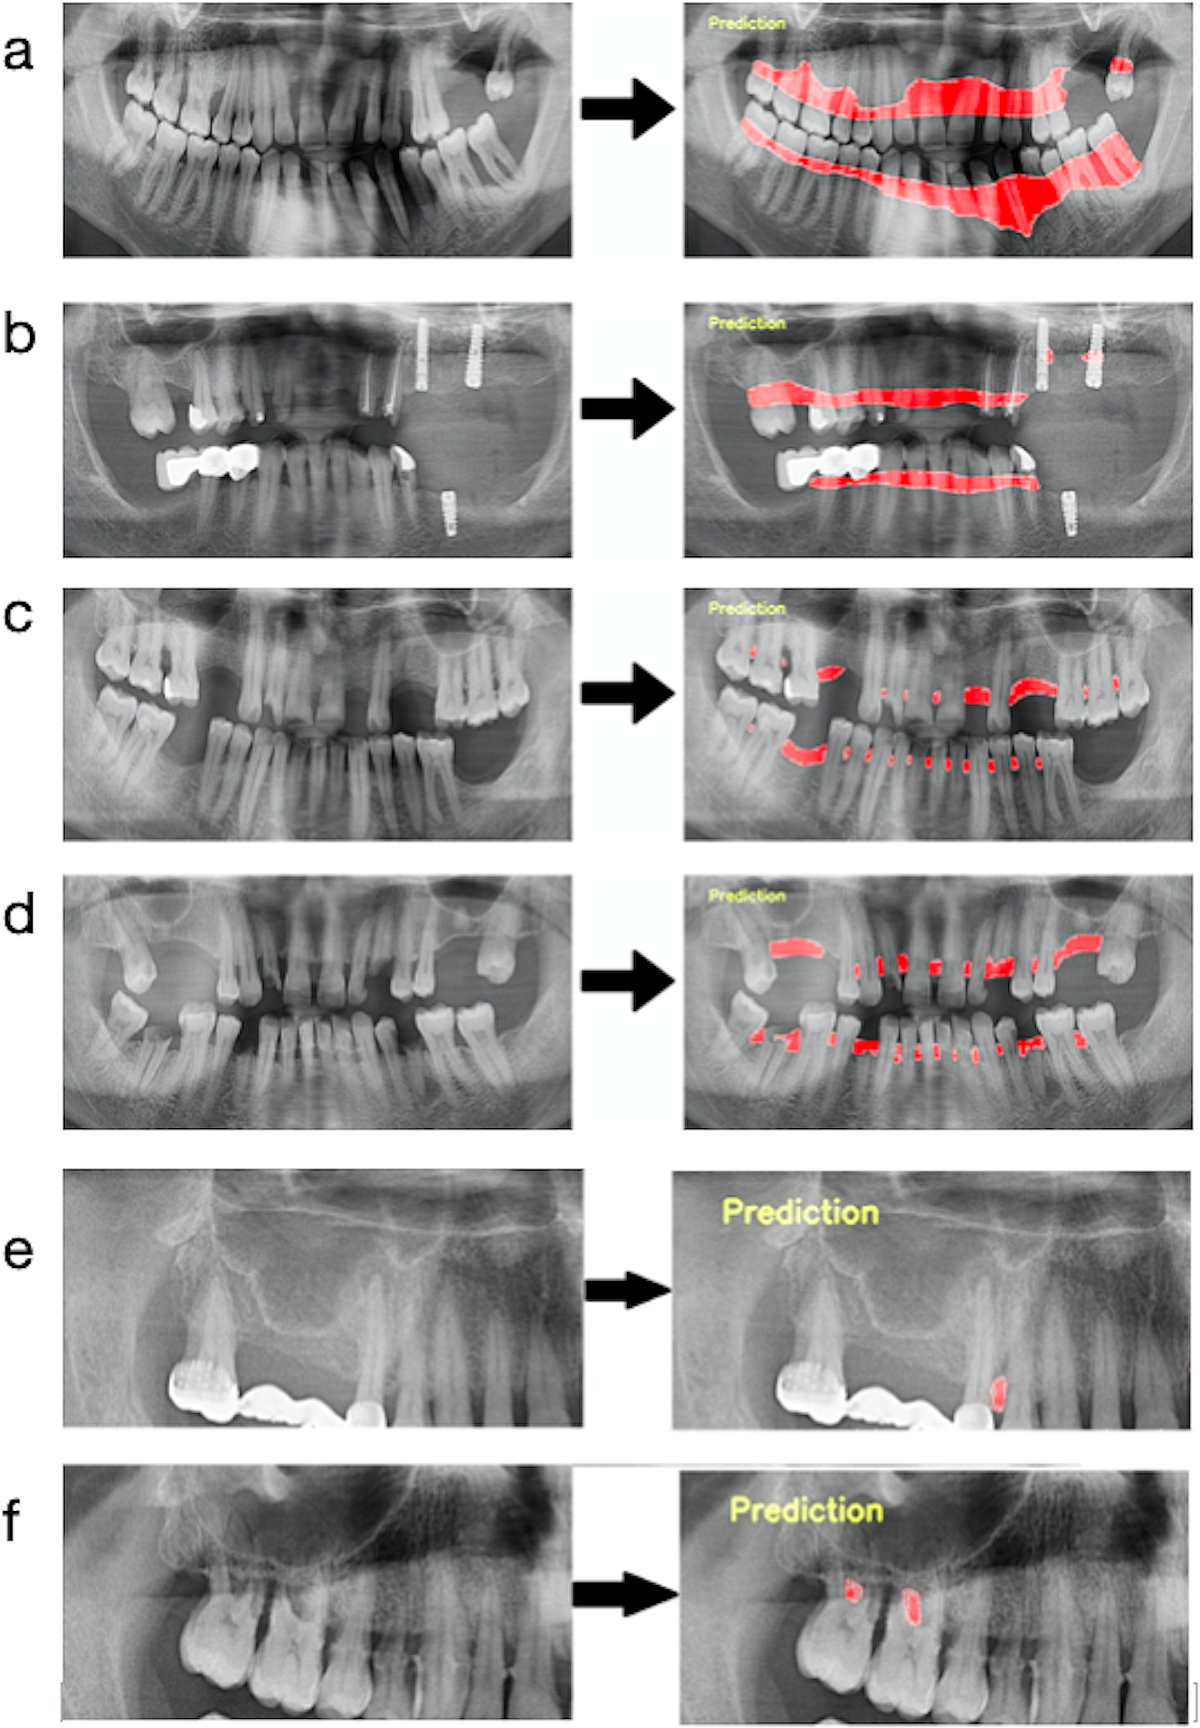

Figure 2. Détection de la perte osseuse parodontale par l’IA (panoramiques)

Six exemples (a–f) : à gauche, la radiographie panoramique d’origine ; à droite, la prédiction de l’IA avec surimpression en rouge des zones de perte osseuse alvéolaire. Sont illustrés une perte horizontale généralisée, l’évaluation du niveau osseux autour d’implants, des résorptions sévères et des lésions localisées ou avec atteinte de la fourche (furcation). Montre l’apport de l’IA pour repérer et délimiter les zones parodontales à risque.